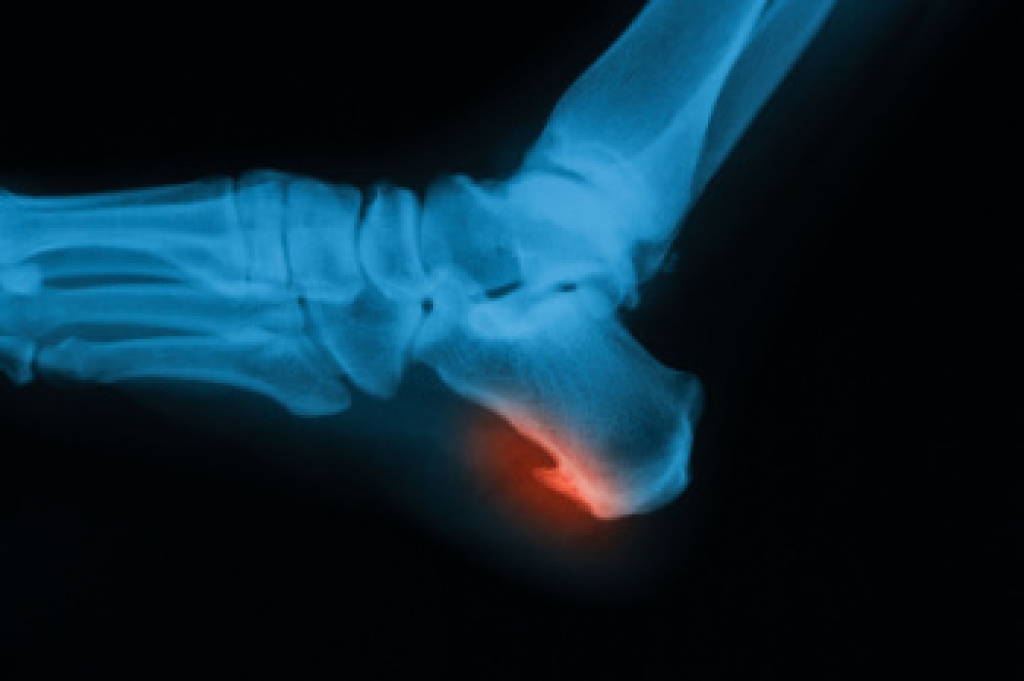

Symptoms vary depending upon the injury and in some cases, there may be no symptoms at all. However, in most cases, some form of symptom is experienced. Pain, aching, burning, bruising, tenderness, tightness or stiffness, sensation loss, difficulty moving, and swelling are the most common symptoms.

Just as symptoms vary depending upon the injury, so do treatment options. A common treatment method is known as the RICE method. This method involves rest, applying ice, compression and elevating the afflicted foot or ankle. If the injury appears to be more serious, surgery might be required, such as arthroscopic or reconstructive surgery. Lastly, rehabilitation or therapy might be needed to gain full functionality in the afflicted area. Any discomfort experienced by an athlete must be evaluated by a licensed, reputable medical professional.